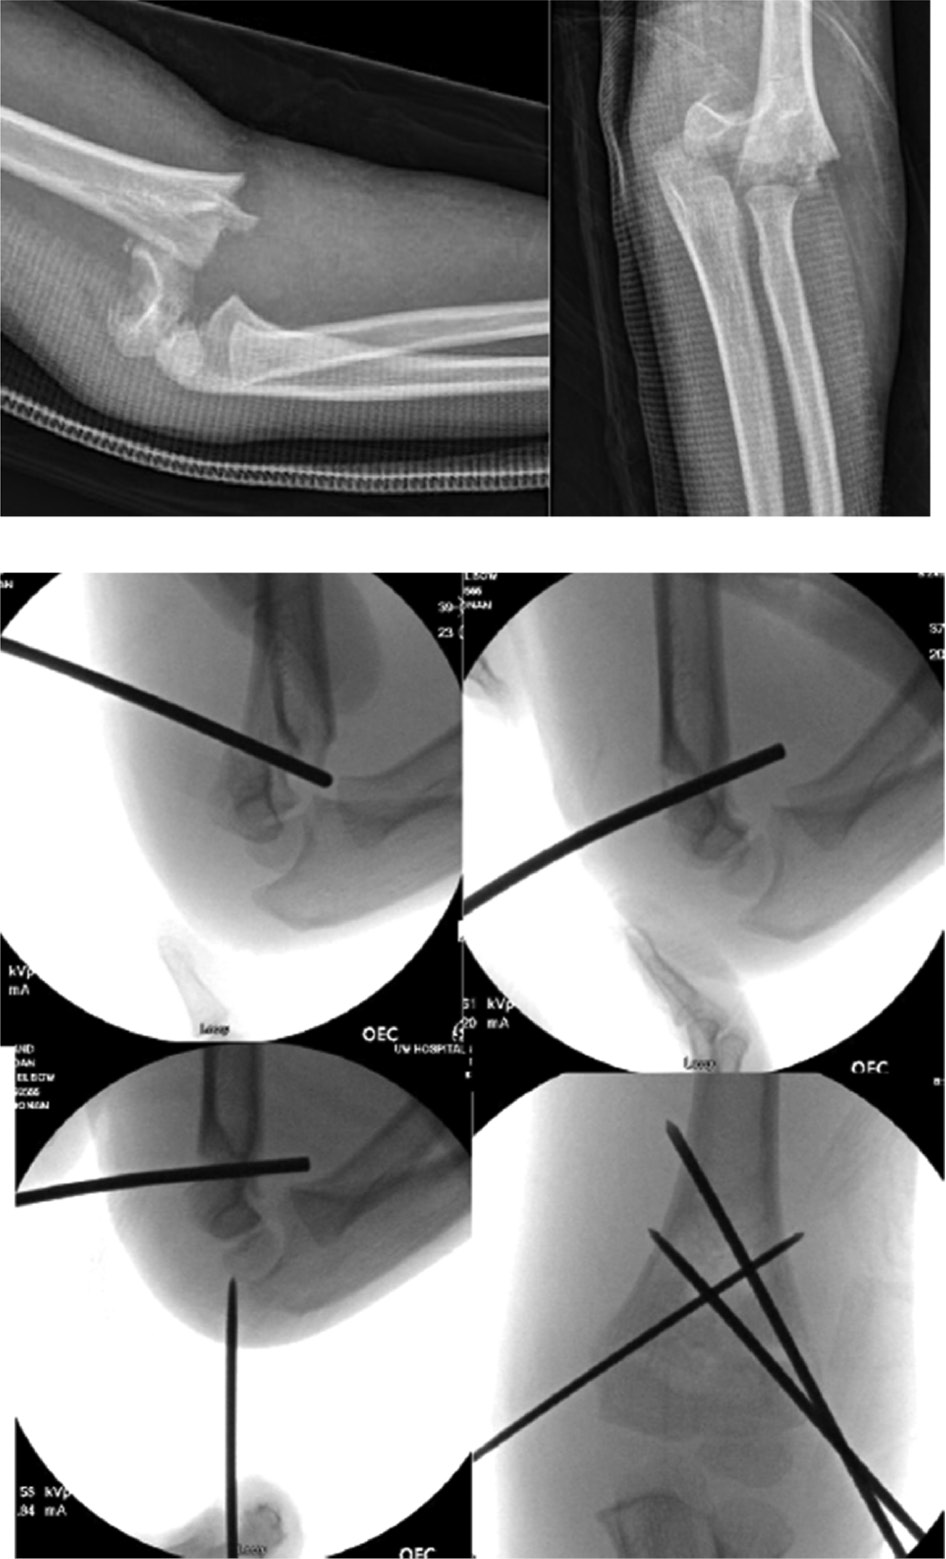

Lateral condyle humerus fracture (LCHF) is the second most common pediatric elbow injury. These injuries are intraarticular and are inherently unstable as the lateral condyle serves as the common extensor origin, which acts as a deforming force, resulting in nonunion of these injuries (Figure 8).33 As such, displaced LCHF are indicated for surgical fixation; percutaneous pinning is associated with shorter operating room times, lower risk of avascular necrosis, lower risk of damage to neurovascular structures, and less soft tissue trauma compared to open reduction and internal fixation.34,35

Figure 8. This child with a lateral condyle fracture underwent percutaneous pin fixation. After the first pin is placed, a cannulated drill bit is reversed and compresses the fracture while a second K-wire is placed divergently to hold the fracture compressed.

Fractures that are displaced greater than 2 mm or those with significant intraarticular involvement are indicated for surgical fixation. Once surgically identified, while preserving the posterior soft tissue attachments, the fragment can be reduced with the use of a K-wires as a joystick while visualizing the joint surface. Once reduced, at least two K-wires are placed bicortically: at least two lateral-to-medial column pins, perpendicular to the fracture line, may be used; alternatively, one may be placed transversely through the trochlea while the other is placed from the lateral column into the medial column36 (Figure 9).

Figure 9. Lateral condyle fractures have a tendency to displace due to pull of extensor mass. Tension band fixation with an absorbable suture can augment pin fixation.